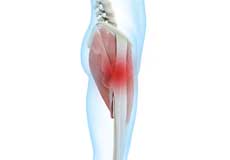

Hamstring Injuries

Hamstring injuries occur when these muscles are strained or pulled. They are common in dancers and athletes of all sorts including runners and those who play football, soccer, basketball, tennis, etc.